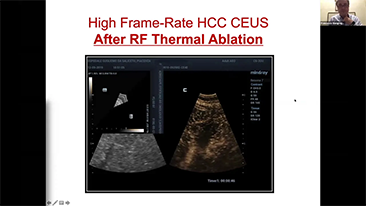

How Clearly Can You See a Liver?

Ultrasound contrast imaging plays a significant role in identifying focal liver lesions, such as hemangioma or liver cancer.

Ultra-wide non-linear UWN+ contrast imaging technology provides better penetration, higher contrast-tissue ratio, with lower MI and longer perfusion time observation.